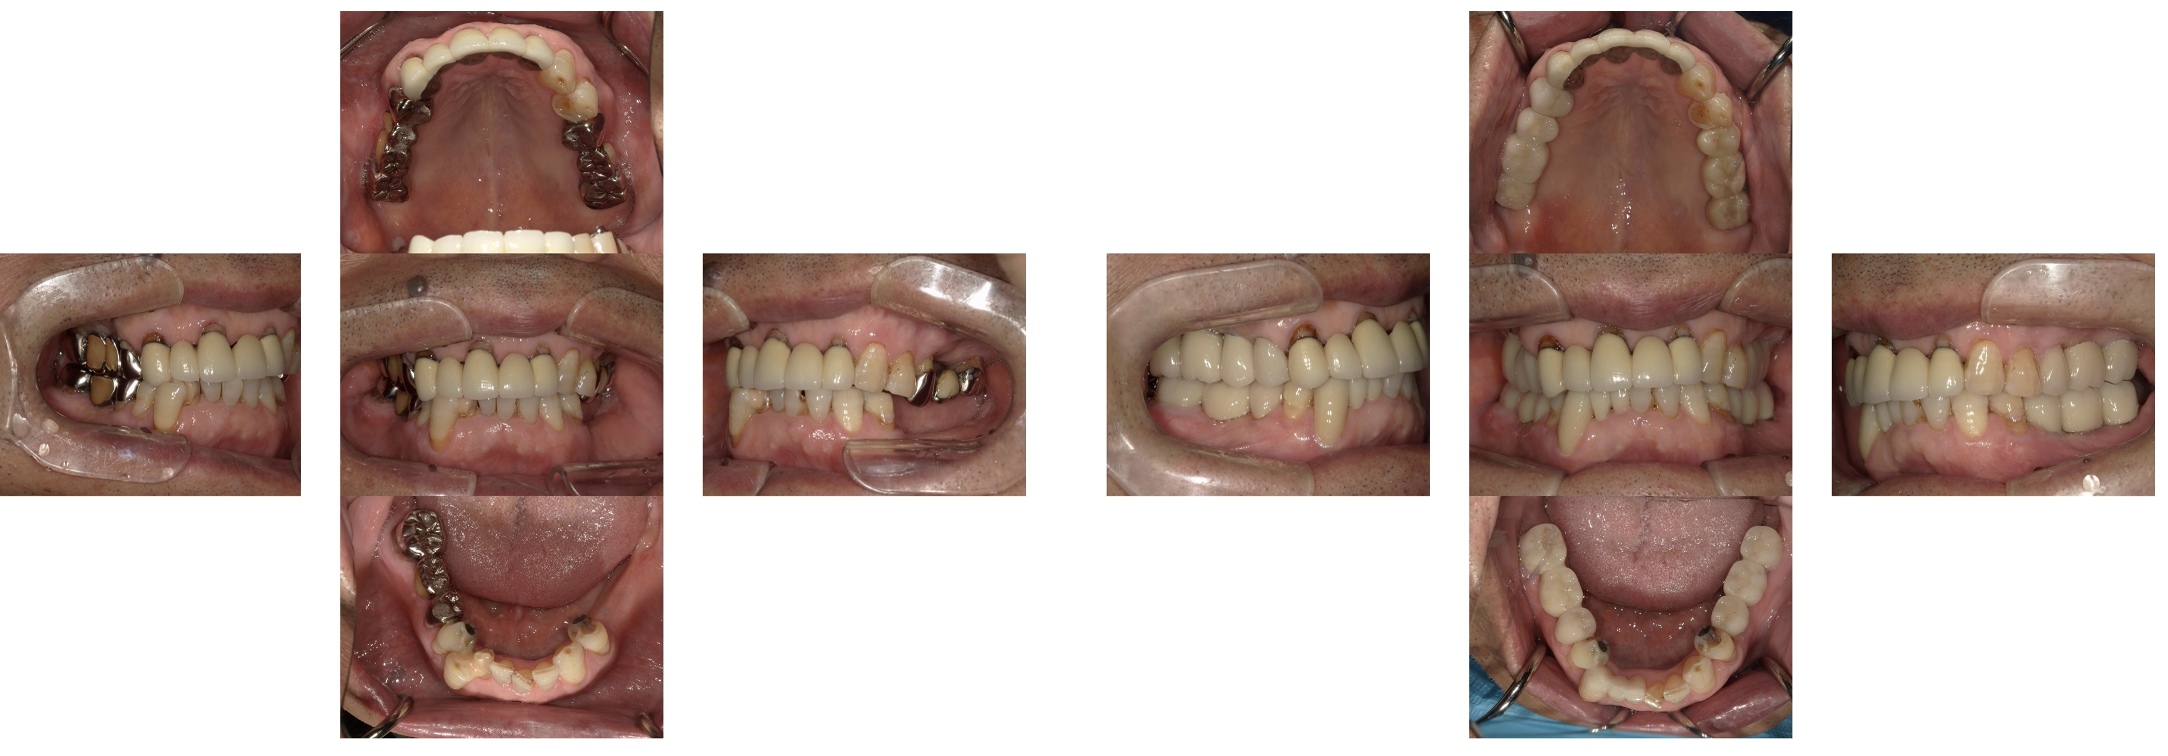

インプラント 症例4

右下56番にインプラントを行い、被せものはブリッジにした症例

虫歯で抜歯した歯にインプラントを行った